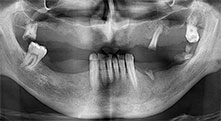

What do you consider the advantages of piezo surgery in relation to oral tissue?

Bratu: I consider piezo surgery a great leap forward in oral surgery. The technique makes bone preparation safer and easier. Little bone is lost, for example in extractions. This is very important in the aesthetic zone, particularly if immediate implantation is planned. Piezo surgery is also safer for soft tissue: injuries to membranes in the sinus are basically history, as are nerve injuries when bone blocks are being harvested. Data indicating reduced postoperative swelling and pain are also available. Piezo surgery is also ideal for preparation of sinus septa. And last but not least, our patients benefit from the atraumatic nature of this technology.